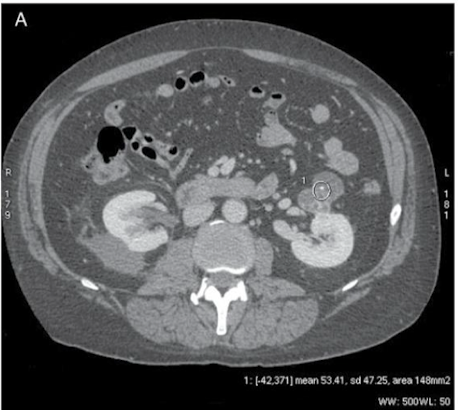

Why is this ROI not appropriate?

Piece of Ca in ROI → SD = 47.25 → make circle smaller so it’s not covering Ca